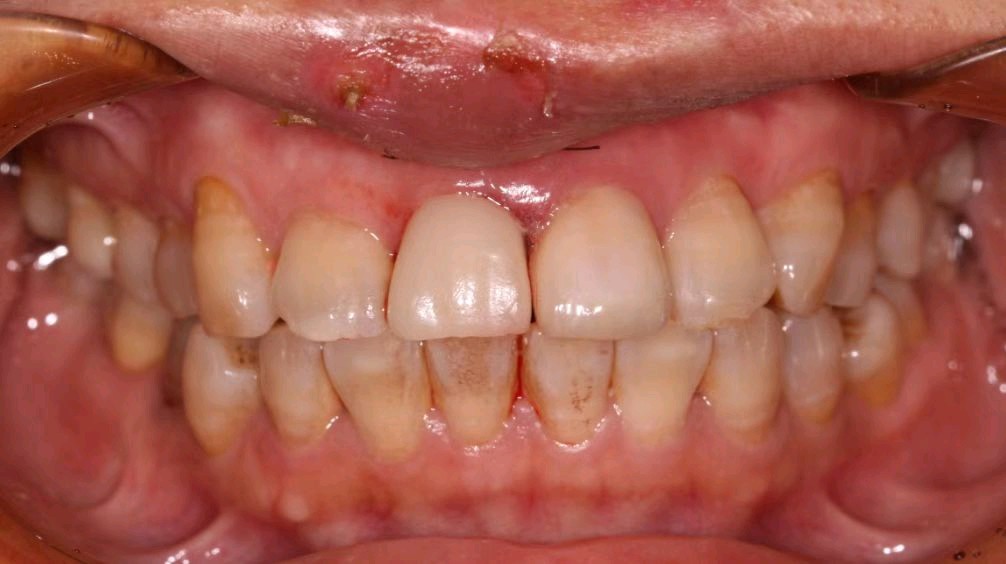

患者右上中切牙外伤导致冠根折,腭侧折面至骨下2mm,需要拔除患牙,x片显示唇腭侧牙槽骨完整,唇侧牙槽骨厚度1.5mm,根尖区剩余牙槽骨也有8mm,符合即拔即种即修复基本条件,患者知情同意下,术前两小时CEREC数字化扫描,设计种植导板,术前准备,拔除患牙,种植导板精密就位,种植窝完成制备,植入植体,拔牙窝间隙中植入Bio-oss骨粉,放置扫描杆,CEREC数字化扫描,一小时后即有一颗和左侧中切牙形态,颜色一致的右侧中切牙,不需要缝合,术后无疼痛,患者非常满意,CEREC数字化技术带给你无限可能!